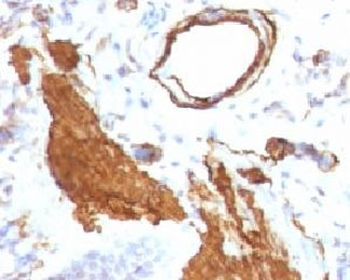

Immunofluorescent staining of fixed human HeLa cells with Smooth Muscle Actin antibody (clone SPM332, green) and NucSpot nuclear stain (red).

IHC: Formalin-fixed, paraffin-embedded Leiomyosarcoma stained with Smooth Muscle Actin antibody (clone SPM332).